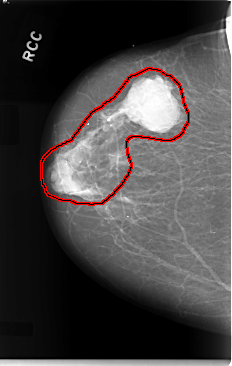

C_0019_1.RIGHT_CC

FILE: C_0019_1.RIGHT_CC.OVERLAY

TOTAL_ABNORMALITIES 1

ABNORMALITY 1

LESION_TYPE MASS SHAPE LOBULATED MARGINS CIRCUMSCRIBED

ASSESSMENT 5

SUBTLETY 5

PATHOLOGY MALIGNANT

TOTAL_OUTLINES 1

BOUNDARY